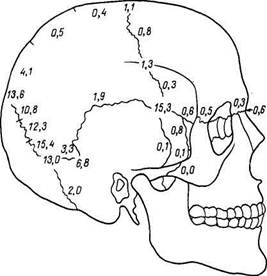

| Рис.34. Непостоянные кости родничков и швов черепа. Цифры обозначают частоту в процентах. |

Соединения между костями черепа представляют главным образом синдесмозы: швы на черепах взрослых и межкостные перепонки (роднички) на черепах новорожденных, что отражает развитие костей свода черепа на почве соединительной ткани и связано с его преимущественной функцией защиты. Почти все кости крыши черепа, за исключением чешуи височной кости, соединяются при помощи зубчатого шва, sutura serrdta. Чешуя височной кости соединяется с чешуйчатым краем теменной кости посредством чешуйчатого шва, sutura squamosa. Кости лица прилегают друг к другу сравнительно ровными краями, sutura plana. Швы обозначаются по имени двух соединяющихся друг с другом костей, например sutura sphenofrontalis, sphenoparietalis и т. п. На основании черепа имеются синхондрозы из волокнистого хряща, находящегося в щелях между костями: synchondrosis petrooccipitdlis, между пирамидой височной кости и pars basilaris затылочной кости, затем synchondrosis sphenopetrosa на месте fissura sphenopetrosa, synchondrosis sphenoethmoidalis на месте соединения клиновидной кости с решетчатой. В молодом возрасте встречаются еще synchondrosis sphenooccipitalis между телом клиновидной кости и pars basilaris затылочной и синхондрозы между четырьмя частями затылочной кости. Синхондрозы основания черепа есть остатки хрящевой ткани, на почве которой развиваются кости основания, что связано с его функцией опоры, защиты и движения. Кроме постоянных швов и синхондрозов, у некоторых людей встречаются еще добавочные, непостоянные, в частности лобный, или метопический, шов, sutura frontalis, metopica (metopion, греч., соответствует лат. glabella) — 9,3 %, при несращении обеих половин чешуи лобной кости.

В швах наблюдаются непостоянные кости черепа: кости родничков, ossa fontieulorum и кости швов, ossa suturalia, частота и положение которых приведены на рис. 34. При рентгенологическом исследовании следует отличать все эти непостоянные кости и соединения костей от повреждения черепных костей.